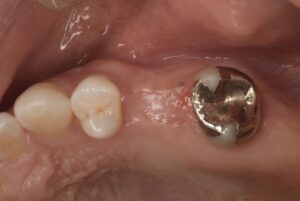

【術前】